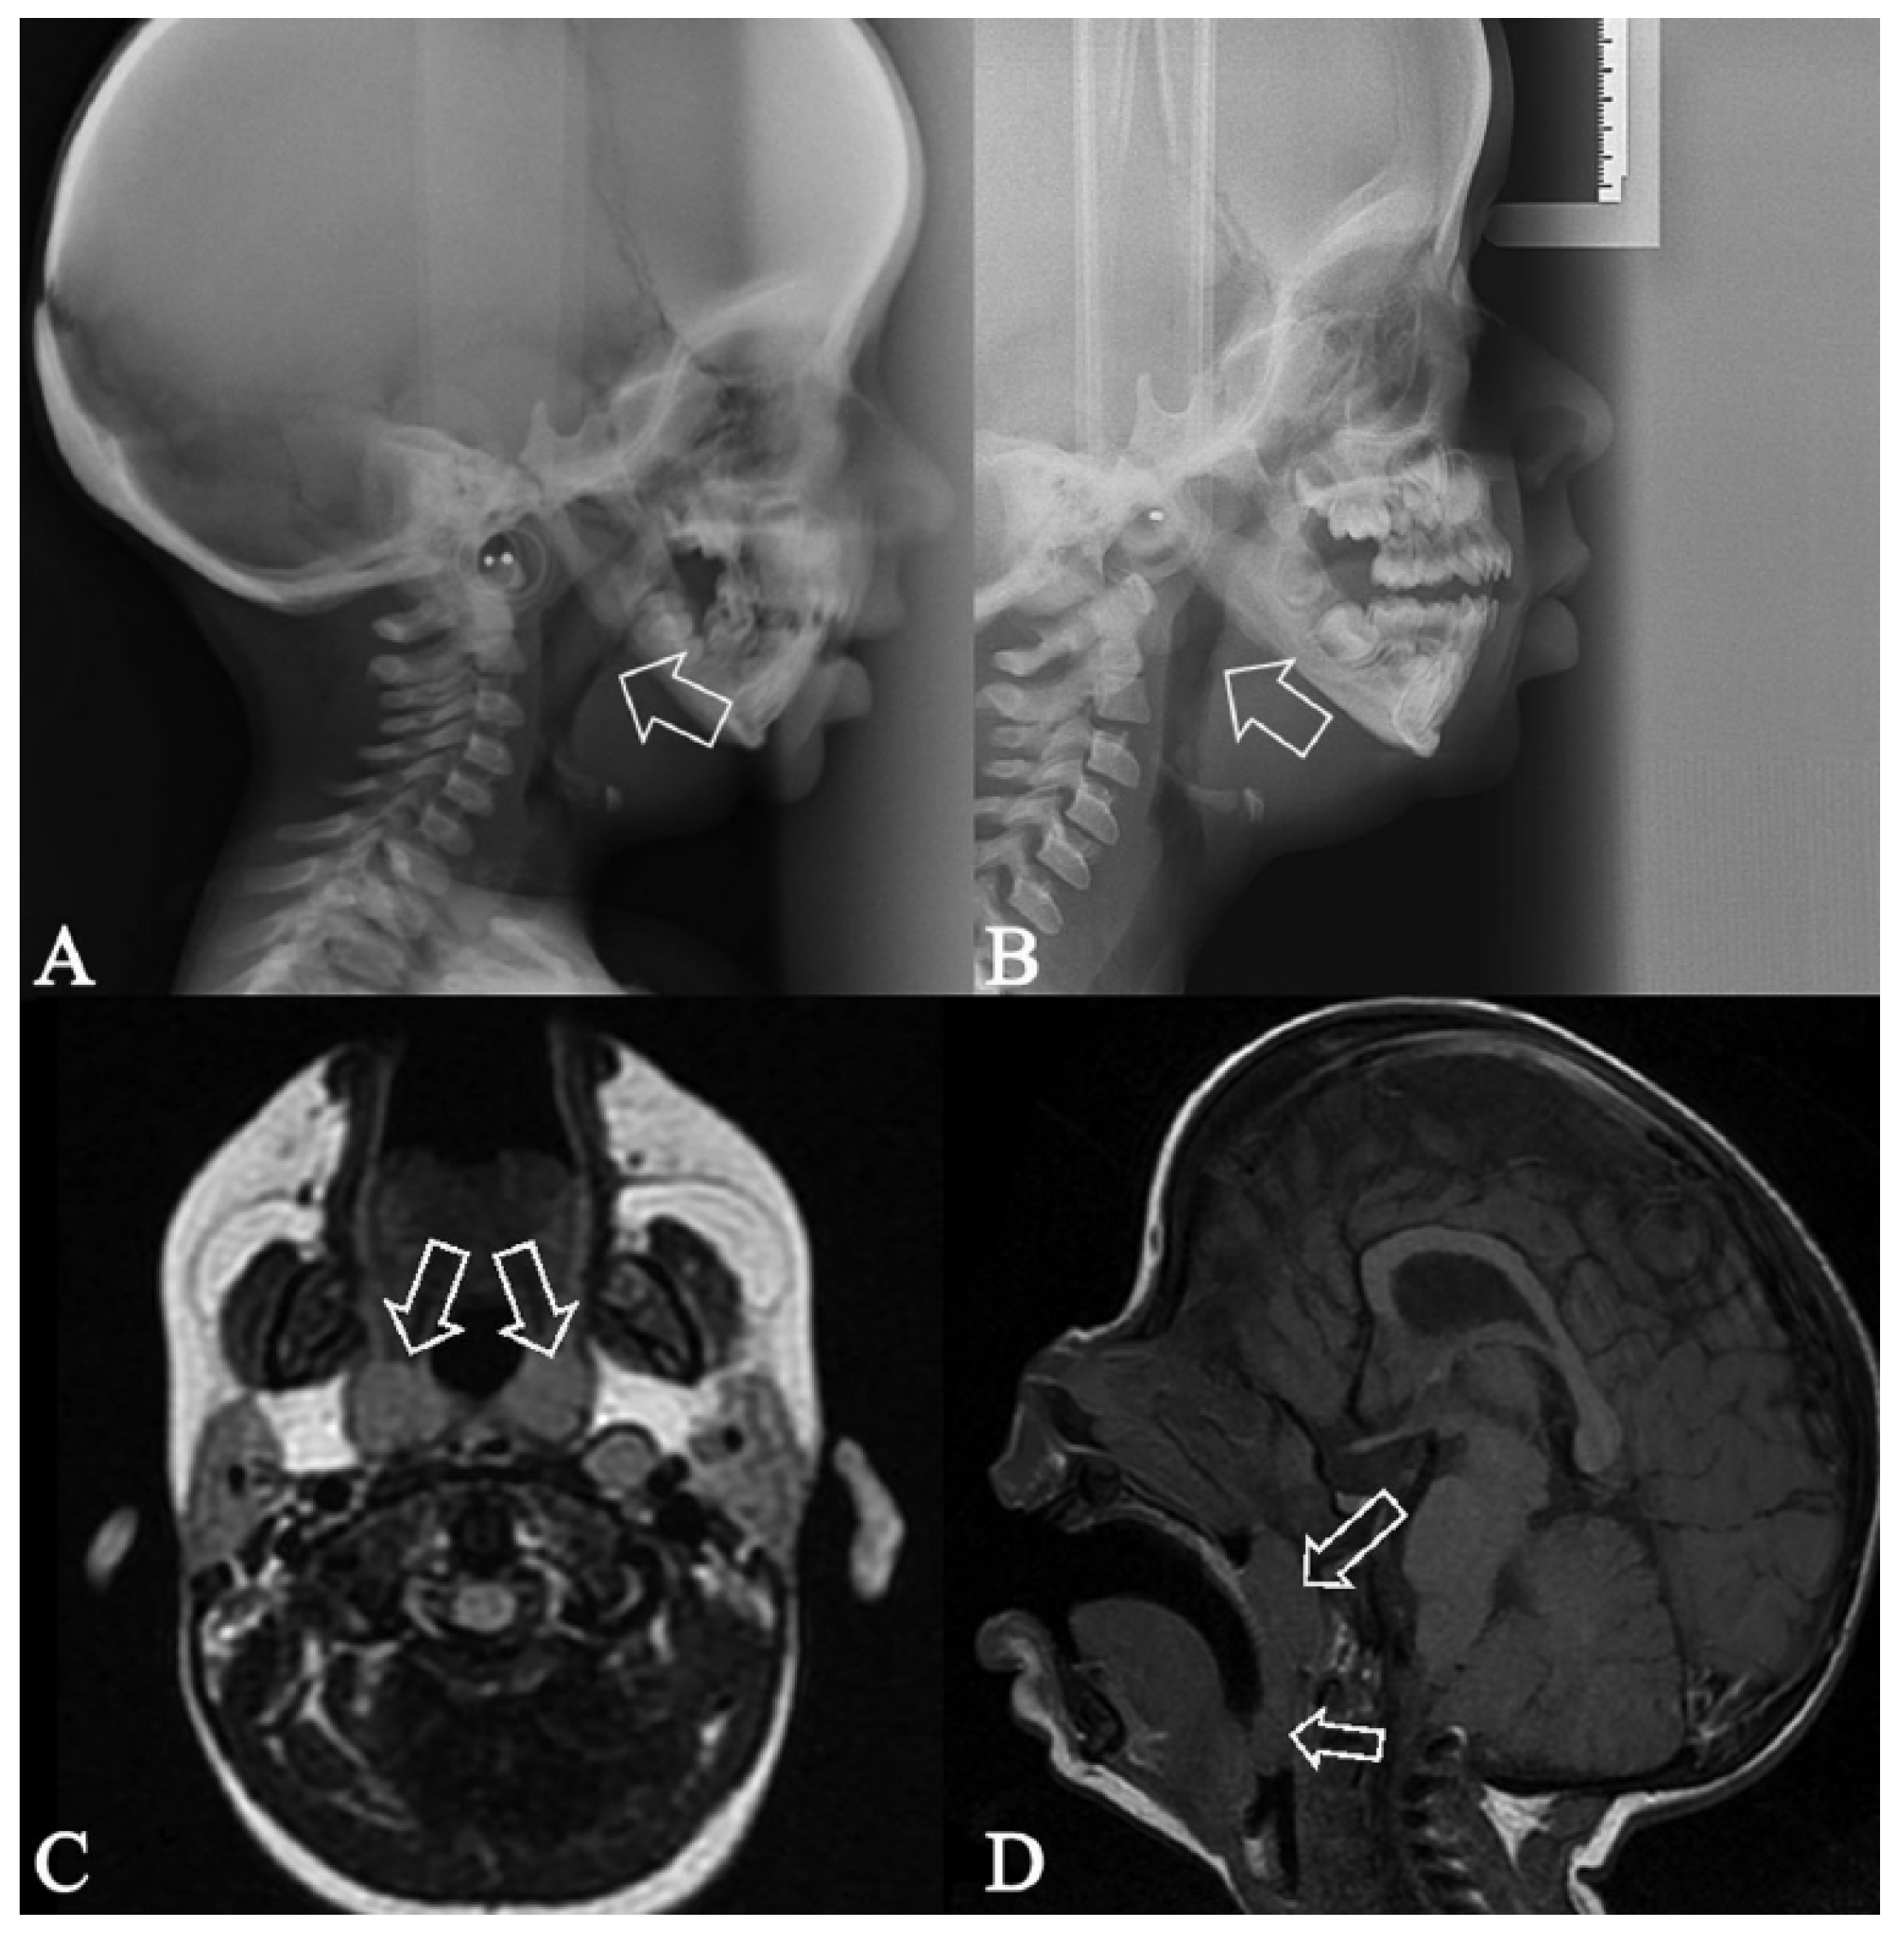

2.2. Diagnosis and Etiology

- Imaging Variability: The pre-orthodontic lateral cephalogram (T2) was performed with the patient’s mouth open. Consequently, the cephalometric analysis focused on dental changes, particularly the inclination of the incisors. A significant limitation of this study is the lack of a reliable quantitative assessment of upper airway volume due to differing patient head positions during the pre- and post-treatment NMR scans. The patient was anesthetized for anxiolysis during the N0 scan, which was taken in a supine, open-mouth position. In contrast, the N1 examination was performed in a supine, closed-mouth position while the patient was awake. Therefore, the upper airway anatomy could not be accurately compared between the NMR scans taken before and after UPP, due to potentially confounding imaging biases [26,27].